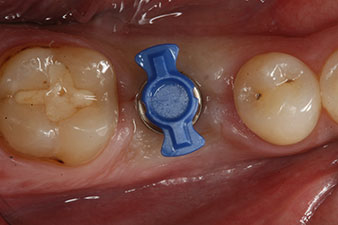

Nach gründlicher Entfernung des Granulationsgewebes wurde das Implantat wie geplant eingebracht (blueSky, bredent).

Das Drehmoment beim maschinellen Einbringen war 43 Ncm. Zusätzlich wurde, nach Einschrauben eines speziellen, auf das Implantatsystem abgestimmten Mess-Pfostens (SmartPeg), der ISQ-Wert mit der Sonde des W&H Osstell ISQ Modul bestimmt.

Dieses Modul ist für das Implantmed von W&H optional erhältlich und wird an den Implantologiemotor gedockt (vgl. Abb. 11). Der dimensionslose ISQ-Wert war direkt bei der Insertion 64 in oro-vestibulärer und 68 in mesio-distaler Richtung (Maximalwert = 100). Dies hätte eine offene Einheilung oder sogar Sofortversorgung erlaubt.